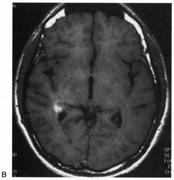

OPTIC TRACTS The optic tract is the continuation of the anterior visual system from the optic chiasm to the LGN. Only the contralateral hemifield is represented. The decussated nasal retinal fibers are not initially well aligned topographically with the other eye's temporal retinal fibers, but retinal correspondence improves towards the termination of the tract at the lateral geniculate nucleus (LGN). The retinotopic map is also tilted in the optic tracts, so that the macula is represented dorsally, inferior retina (superior visual field) laterally, and superior retina (inferior visual field) medially (see Chapter 4, Fig. 9).1 The magnocellular and parvocellular axons also may be segregated, with magnocellular axons more ventral.2 Both of these topographies are mirrored in the LGN. The main vascular supply of the optic tract is the anterior choroidal artery. The functional anatomy of the optic tract is reflected in several important clinical findings. First, partial lesions cause contralateral homonymous defects that can be markedly incongruous (different patterns of visual loss in the two eyes) because of the poor topographic alignment of the two retinal maps (Figs. 1 and 2).3,4 In contrast, lesions of the optic radiations cause only mild incongruity and striate lesions are highly congruous. Complete transection of the optic tract leads to congruous complete hemianopia, although this is less frequent than partial lesions. Reduced acuity with an optic tract lesion indicates bilateral tract damage or extension of the lesion to the optic chiasm or optic nerves.4,5 Second, because the axons in the optic tract originate from retinal ganglion cells, damage to the tract causes optic atrophy over time. This is present in both eyes, but because only half or less of the axons of each eye are affected, the atrophy is less severe than with most optic neuropathies. Also, the pattern of optic atrophy differs between the eyes. In the eye with temporal field loss, the axons from the nasal retina are affected. The fibers from the nasal periphery enter the nasal side of the disc, whereas those from the nasal macula enter the temporal disc in the papillomacular bundle. Atrophy is seen in these nasal and temporal wedges of the disc but the superior and inferior sectors are spared, because these contain fibers from the temporal retina. The result is “bow-tie” optic atrophy (see Fig. 1). In contrast, atrophy in the eye with nasal field loss affects the superior and inferior wedges and papillomacular bundle, but not the nasal wedge. This appears as diffuse or temporal disc pallor. Another distinctive optic disc picture occurs in the eye with temporal field loss when a mass lesion causes papilledema and compresses the optic tract. Disc swelling occurs in the superior and temporal disc but not in the atrophic bow-tie regions, creating “twin-peaks” papilledema (see Fig. 2).6,7 Third, because fibers for the pupillary reflex also travel in the optic tract, often there is a relative afferent pupillary defect (RAPD). With a significantly incongruous hemianopia, the RAPD may be in the eye with greater visual loss. With a complete tract lesion the RAPD is in the eye with temporal field loss,4,8 because the temporal hemifield is larger and there are slightly more axons from the nasal than temporal retina (ratio 53:47). The RAPD is a useful sign in optic tract hemianopia because it may be present at a time when optic atrophy has not yet developed (see Chapter 15).9 Other reported pupillary abnormalities include Wernicke's hemianopic pupil, which is an intraocular afferent pupil defect, with less pupillary constriction from light on the hemianopic hemiretina compared to light on the intact hemiretina. Wernicke's hemianopic pupil is difficult to elicit at the bedside because of intraocular light scatter,3 although it may be seen with computerized pupillometry (Fig. 3). The combination of optic atrophy, RAPD and field incongruity is important to recognize with homonymous hemifield defects, because it changes the differential diagnosis of hemianopia (Fig. 14). Most hemifield defects from lesions of striate cortex or the optic radiations result from vascular disease or other intracerebral pathology. Most optic tract lesions are compressive extrinsic masses, with a differential diagnosis similar to that for optic chiasmal lesions (see Chapter 6). In fact, patients with combined damage to the optic tracts, chiasm, and nerve are not rare.4,10–13 Pituitary adenomas, giant aneurysms of the internal carotid artery, meningiomas, and craniopharyngiomas are the chief causes of optic tract dysfunction. The investigation of choice is imaging of the parasellar region, with coronal and axial sections and contrast administration. Less common lesions include inflammatory conditions such as multiple sclerosis3,11,14,15 and sarcoidosis (see Fig. 1).16 Intrinsic optic pathway gliomas may occur in the optic tracts. Vascular lesions are rare, but there are reports of cavernous angiomata10,17 or arteriovenous malformations.18 Optic tract infarction can complicate anterior temporal lobectomy, possibly from vasospasm of the anterior choroidal artery.19 Trauma can affect the optic tract.3 Radiotherapy of pituitary tumors may be followed years later by optic tract necrosis.13 Optic tract dysfunction is a side effect of alpha-interferon.20 On occasion there is congenital absence of the optic tract 21; such patients are often unaware of their hemianopia. Associated abnormalities are unusual.3 These include endocrine disturbances from hypothalamic dysfunction and memory impairment from temporal lobe involvement,22 reflecting the proximity of the optic tracts to these structures (see Chapter 4). LATERAL GENICULATE NUCLEUS The LGN is a subnucleus in the ventro-postero-lateral corner of the thalamus. Neighboring thalamic subnuclei include the medial geniculate nucleus ventromedially, ventral posterior nucleus dorsomedially, and pulvinar superiorly and dorsally. The medial geniculate nucleus gives rise to the acoustic radiations, which pass by the dorsomedial aspect of the LGN on their way to the auditory cortex in the temporal lobe. The optic radiations arise from the dorsolateral surface of the LGN. Ventrally, the hippocampus and parahippocampal gyrus face the LGN across the ambient cistern and the inferior horn of the lateral ventricle. The LGN has a dual blood supply: the anterior choroidal artery, a branch of the internal carotid artery, and the lateral choroidal artery, a branch of the posterior cerebral artery. The anatomy of the vascular territories within the LGN has been debated. Initial studies suggested that the anterior choroidal artery supplied the medial LGN as well as the optic tract and the lateral choroidal artery the lateral LGN. However, experience with surgical arterial lesions concluded that the anterior choroidal artery supplied both the lateral and medial aspects and the lateral choroidal artery supplied the hilus and midzone of the LGN. In addition to its function as a relay in the visual pathway, the LGN is also a site of modulation, by back-projections from visual cortex23,24 and afferent projections from the brainstem reticular formation and superior colliculus.25 Some of the corticofugal input influences the stimulus selectivity of LGN neurons.24 Others postulate that these nonretinal inputs play a role in gating visual transmission through the LGN, and thus participate in selective attention.23 The LGN is a triangular shaped structure with six roughly horizontal layers containing segregated inputs from the two eyes (see Chapter 4, Fig. 8). The ventral two layers are the magnocellular layers, whereas the other four layers are the parvocellular component; these differ in many structural and functional aspects (see Chapter 4). The LGN has a retinotopic pattern that is a continuation of that found in the optic tract. The macula is represented in a dorsal wedge, including the hilum and projecting posteriorly, whereas the most peripheral fibers are located ventrally. Superior retinal fibers (contralateral inferior visual quadrant) are in the medial horn and inferior retinal fibers (contralateral superior visual quadrant) are in the lateral horn. Because the LGN is small and relatively secluded, lesions here are rare. Its intimate relation to the optic tract and optic radiation make it difficult to be certain that a visual defect results from LGN damage rather than damage to these structures. Indeed, visual field defects from purported LGN lesions resemble visual field defects from optic tract or optic radiation lesions. Three main types of hemianopic defects have been described. The first is an incongruous hemianopia, much like that seen with optic tract lesions, reflecting the continued segregation of ocular inputs in the LGN. The other two patterns are sectorial hemianopias reflecting the unusual territorial division between the anterior and lateral choroidal arterial supplies. With lateral choroidal ischemia, the hilum and middle zone of the LGN are affected, causing a wedge-shaped visual defect straddling the horizontal meridian (Fig. 4).26 With anterior choroidal ischemia, the lateral and medial tips of the LGN are infarcted, resulting in the reverse defect, loss of the superior and inferior aspects of the contralateral hemifield with sparing around the horizontal meridian.27,28 Unusual cases of presumed bilateral LGN damage have presented with an “hourglass” shape to either the visual field defect29,30 or the region of spared vision.31 Optic atrophy often accompanies LGN lesions. If there is damage to almost all of the LGN, the optic atrophy has a similar appearance to that seen with optic tract lesions. If there is partial damage causing sectorial hemianopias, then the optic atrophy may be more subtle and restricted to the relevant sectors of the disc.26,27 However, because the afferent fibers subserving the pupillary light reflex already have departed for the pretectum, there is no RAPD with lesions of the LGN. With incongruous hemianopia and optic atrophy, this is the only feature that permits distinction between optic tract and LGN lesions. A variety of pathologies have been reported with LGN lesions. Infarction is the most likely cause of sectoranopia, given the dependence of such defects on the vascular anatomy,26,27 but astrocytomas and arteriovenous malformations are also reported. Furthermore, the LGN appears to be a target of central pontine myelinolysis, a syndrome associated with excessively rapid correction of hyponatremia.29,30,32 LGN damage rarely is a parainfectious complication of traveler's diarrhea.31 OPTIC RADIATIONS The optic radiation may be affected anywhere in its course (see Chapter 4); the type of visual field defect reflects the site of damage. Ischemic or hemorrhagic lesions of the internal capsule affect the optic radiation while it is still a relatively compact bundle, usually causing a complete homonymous hemianopia. A similar defect can arise from damage close to the termination in striate cortex (Fig. 5). Lesions of the ventral fibers in the anterior temporal lobe cause a contralateral superior visual quadrant defect (Fig. 6). Most often this defect aligns on the vertical meridian, with variable extension toward the horizontal meridian and central vision.33 Lesions of the dorsal fibers in the parietal lobe cause an inferior visual quadrant defect (Fig. 7). Because there is no sharp demarcation of the dorsal fibers from the ventral fibers in this portion of the posterior pathway, the defect seldom aligns along the horizontal meridian.33 Overall, quadrantanopia is more frequent with lesions of striate cortex.33 Lesions of the temporal lobe more than 8 cm posterior to its anterior tip can affect both upper and lower radiations. Small lesions also may affect certain portions of the radiations and spare others; for example, damage to the midportion of the optic radiation can mimic the sectoranopias of LGN lesions (Fig. 8).34 Although there can be some incongruity to the visual field defects of optic radiation lesions, this is less marked than the incongruity with optic tract lesions. Unlike lesions of the retino-geniculate pathway or LGN, lesions of the geniculostriate axons do not lead to optic atrophy (with the exception of some congenital lesions, through trans-synaptic degeneration) or pupillary defects. However, frequently there are other signs of cerebral damage,33 especially if the lesion is large. Thus, temporal lobe lesions cause superior quadrantic defects and sometimes also complex partial seizures, auditory or complex visual hallucinations (some of which may be seizures), memory problems, or a Wernicke's aphasia if the dominant hemisphere is involved. Parietal lesions with mainly inferior quadrantic defects may cause cortical sensory disturbances, such as impaired two-point discrimination and graphesthesia, and impaired smooth pursuit toward the side of the lesion. With dominant hemisphere lesions, Gerstmann's syndrome (acalculia, finger anomia, right-left disorientation, and agraphia) may occur, as may a variety of aphasic syndromes, including alexia with or without agraphia, Wernicke's aphasia, or global aphasia. The differential diagnosis of optic radiation lesions reflects the variety of cerebral hemispheric pathologies. Unlike lesions of the optic tract, most are infarcts in the posterior cerebral or middle cerebral artery territories. Tumors, vascular malformations, infections, and leukodystrophies are also possibilities. The temporal profile of the illness often is the major clue to the etiology. STRIATE CORTEX The primary visual area in the medial occipital lobe goes by several names: Brodmann's area 17, “visual area 1” or V1, “calcarine cortex,” and “striate cortex” (see Chapter 4). The exact position of striate cortex varies among individuals. Although the parieto-occipital fissure forms a reasonably reliable anterior dorsal boundary, the posterior limit containing the macular representation is more variable, extending from the medial occipital surface over the first one or two centimeters of the posterior surface of the occipital lobe (see Chapter 4, Fig. 10). The main vascular supply of striate cortex derives from the posterior cerebral artery (see Chapter 4, Fig. 15). A parieto-occipital branch supplies the superior calcarine bank, a posterior temporal branch supplies its inferior bank, and a calcarine branch supplies the central region posteriorly; however, individual variation exists.35 Perhaps most importantly, the occipital pole is at the junction (watershed zone) of the vascular territories of the posterior and middle cerebral arteries, and again there is marked variation as to which artery supplies the foveal representation in striate cortex.35 The retinotopic arrangement in striate cortex is well known (see Chapter 4), and confirmed with recent imaging studies of lesions.36 The foveal representation is posterior, at the occipital pole, and the far peripheral field is anterior, on the medial occipital surface.37,38 The superior bank of the calcarine fissure receives input from the inferior visual field, whereas the inferior bank contains the representation of the superior visual field. The most anterior part of striate cortex represents the monocular temporal crescent, the region of temporal field in the contralateral eye that lies beyond the limits of the nasal field (60°) of the ipsilateral eye. As in most of the visual system, there are fewer neurons devoted to peripheral vision than to central vision: Over half of striate cortex is devoted to the central 10° (cortical magnification).36,39 Occipital cortex contains a mixture of monocular and binocular cells arranged in ocular dominance columns, but large separations between the inputs of the two eyes are not present. Visual Field Defects from Striate Lesions Focal destruction of striate cortex produces a homonymous contralateral visual hemifield defect. Unlike the scotomata from lesions of the optic radiations and especially the optic tracts, the hemianopic defects from striate lesions are highly congruent, with virtually identical defects in the two eyes. Complete destruction of striate cortex causes complete visual loss in the contralateral visual hemifield. Because this involves not only peripheral vision but also the contralateral half of the foveal region it is called a macula-splitting homonymous hemianopia. This may occur with posterior cerebral artery ischemia in a patient whose entire striate cortex is supplied by that artery. Macula-splitting hemianopias can occur with complete lesions anywhere along the retrochiasmal visual pathways, and thus lack localizing value (see Fig. 5). Other signs may help in localization. Reading is particularly impaired by involvement of the central 5°.40 Partial lesions of the striate cortex are frequent. With posterior cerebral infarcts, a macula-sparing hemianopia occurs in patients with adequate collateral circulation of the macula region (occipital pole) from the middle cerebral artery (Fig. 9).35 Previously, macula-sparing was thought to result from bilateral representation of a small stripe flanking the vertical meridian, which expanded to as much as 3° at the fovea.41 However, studies of monkey V1 do not find bilateral representation of the hemimaculae,42 and computed tomography (CT) and magnetic resonance imaging (MRI) studies in humans with hemianopia document the correlation of macular sparing with sparing of the occipital pole.43,44 Also, careful perimetry of hemianopes with the scanning laser ophthalmoscope shows that, although there is a slight overlap from the seeing field into the blind field along the meridian, macular sparing of 2° to 5° is only present in some patients.45,46 Therefore sparing more likely reflects the extent of occipital pathology than retinal anatomy. Macula-sparing has some localizing value, because it is seen mainly with lesions of striate cortex. The upper and lower banks can also be involved separately. Ischemia can do this because the banks have separate blood supplies. Upper bank infarcts cause homonymous contralateral inferior quadrantanopia (Fig. 10) and lower bank infarcts cause superior quadrantanopia. Although altitudinal defects have been reported occasionally,47,48 most quadrantic defects do not align at the horizontal meridian, because the upper field merges without interruption into the lower field in the depths of the calcarine fissure. Thus it has been argued that quadrantic defects that respect the horizontal meridian are caused by involvement of area V2, surrounding striate cortex,49 which remains controversial. Quadrantanopias are three times more common with striate lesions than with optic radiation lesions.33 Striate quadrantanopias are more frequently isolated signs but can be associated with other signs of higher cortical visual dysfunction, such as pure alexia or hemiachromatopsia, whereas optic radiation quadrantanopias usually are accompanied by hemiparesis, dysphasia, or amnestic problems.33 Selective lesions can also occur along the anterior-posterior extent of striate cortex. A lesion of the occipital pole alone causes homonymous central hemiscotomata (Fig. 11).44,50 This can occur with watershed infarcts during systemic hypoperfusion. Slightly more anterior lesions in the middle zone of striate cortex cause homonymous peripheral scotomata (Fig. 12). The highly congruent, homonymous nature of these defects and their restriction to one hemifield differentiate these from ocular causes of central or paracentral visual loss. Lesions with such small field defects can be missed on CT.43 MRI with coronal sections through the occipital lobes should be performed, although even this may miss small lesions, particularly at the occipital pole. A near-complete lesion that spares only the most anterior portion of V1 causes a nearly pathognomonic field defect, hemianopia with sparing of the monocular temporal crescent (Fig. 13). The hemianopia involves the whole nasal hemifield of the ipsilateral eye but the temporal hemianopia of the contralateral eye spares a crescent-shaped island of vision in the far periphery.51 This is the monocular temporal crescent, the region of the visual field that is represented in the temporal field of one eye but not the nasal field of the other. The initial sense of incongruity may raise suspicions of an optic tract lesion; however, the absence of optic atrophy and RAPD, the high congruity of the homonymous defect inside 60°, and the location of the crescent outside 60° eccentricity, indicate that the lesion must be in striate cortex. The converse defect, a monocular temporal crescentic scotoma, can occur with a retrosplenial lesion, along the parieto-occipital sulcus.52 Most striate lesions are infarction, mainly from posterior cerebral artery occlusion (Fig. 14), with sudden onset visual loss and sometimes headache.53 In about half, the visual field defect is the only deficit,53 but in others damage to medial occipito-temporal regions causes amnesia, prosopagnosia, and color perception defects. A syndrome of agitated delirium and hemianopia occurs with lesions of the medial occipital lobe, parahippocampus, and hippocampus.54–56 Brainstem signs include impaired level of consciousness, III nerve palsy, dysarthria and hemiplegia.53 Causes of ischemia are most frequently cardiac emboli and vertebrobasilar occlusive disease; migraine is a rare cause of permanent defects.53 Hemorrhage, vascular malformations, primary and secondary malignancies are much less common.33 Bilateral lesions of striate cortex are not rare. Focal midline lesions such as tumors or traumatic injury may affect both striate cortices concurrently, because the right and left striate cortices face each other on the medial occipital surface. The most common cause, however, is posterior circulation ischemia.57 This can affect both striate cortices either simultaneously or sequentially,57 because the right and left posterior cerebral arteries have a common origin from the basilar artery. Twenty-two percent of patients with a unilateral occipital infarction develop bilateral infarction over 3 years.58 Bilateral incomplete hemianopia is distinguished from bilateral optic nerve or ocular disease by the high congruity of the visual fields and step defects along the vertical meridian which indicate the hemifield nature of the visual loss (Fig. 15).57 Such steps are important to seek with a skilled perimetrist, but even so they can be difficult to demonstrate with bilateral hemiscotomata from occipital pole lesions.59 Bilateral quadrantanopias can occur,47,48 often in patients with prosopagnosia and achromatopsia for example, and may mimic the altitudinal defects of optic neuropathy. Cerebral Blindness Cortical blindness is a loosely used term, at times referring to visual loss from occipital lobe damage, even if the loss is incomplete. Hence hemianopia or bilateral quadrantanopia has been called cortical blindness. It is best reserved for bilateral complete or severe hemianopia, with acuity at light perception only or worse, and no detectable peripheral vision. Because lesions may involve both gray and white matter, cerebral blindness is a better term. Cerebral blindness can be persistent or transient. The most frequent cause of persistent cerebral blindness is cerebrovascular infarction.60 In addition to the common causes of emboli or atherosclerosis, it has been reported with vertebrobasilar arteritis,61 subclavian steal,62,63 and hypotension from antihypertensive medication.64,65 Cerebral blindness can complicate cardiac surgery, through hypotension or emboli.60 A rare vascular cause is rupture of occipital mycotic aneurysms with endocarditis.66 Cerebral blindness is distinguished from ocular disease by both normal pupillary light responses and normal fundoscopic examination. These may lead to an erroneous diagnosis of factitious visual loss. Associated signs of damage to parietal or temporal structures help to confirm cerebral blindness but may not always be present. Visual evoked potentials are of limited diagnostic value. They can be altered voluntarily by subjects without visual loss67 and can be normal in patients with striate lesions.68,69 They cannot differentiate between blind and seeing children with neurologic disease,70 and normal or abnormal results do not predict visual outcome.60,71 Absent evoked responses are rare and may only occur early in the course.70 Absent alpha rhythm on electroencephalography72,73 is reportedly a more sensitive diagnostic sign than abnormal visual evoked potentials.60 CT scans can be normal, but modern MR imaging with coronal images through the occipital lobe should reveal most striate or optic radiation lesions with complete and persistent visual loss (Fig. 16). Single photon emission computed tomography (SPECT) scans may reveal bilateral functional defects in cases with unilateral MRI lesions.74

Among adults with infarction, blindness is permanent in 25%57 and residual visual field defects are common in the rest. Bioccipital CT lucencies carry a poor prognosis for recovery, but abnormal visual evoked potentials do not correlate with severity or outcome.60 Although the abnormalities on visual evoked potentials are not diagnostic, they tend to improve as vision returns.75–77 Transient cerebral blindness can last hours to days, often with full recovery (Table 2). Both ictal and post-ictal cerebral blindness are reported in children and adults.78–80 Transient cerebral blindness can occur with metabolic insults,81–83 hypertensive encephalopathy,84 hydrocephalus,85 trauma,72,86 and cortical venous thrombosis.87 Toxins are an important cause, especially chemotherapeutic agents.88–92 Cerebral blindness is associated with the iodinated contrast agents used in angiography:60,93,94 CT scans with contrast show disruption of the blood–brain barrier in the occipital lobes93,94 as early as 1 hour after angiography.95 TABLE 2. Causes of Transient Cerebral Blindness